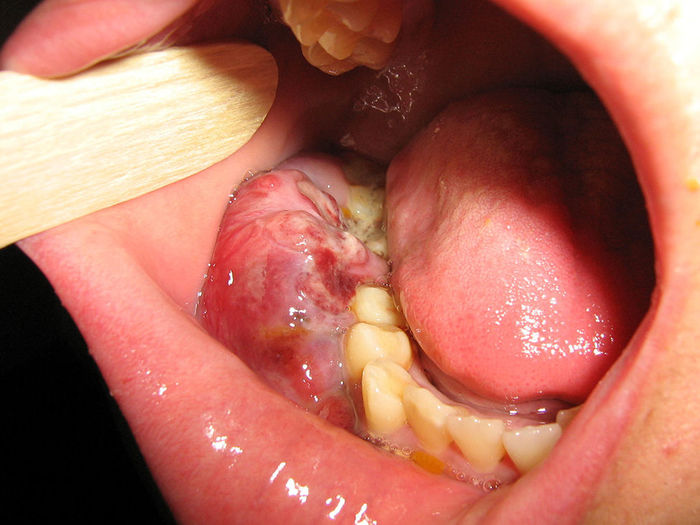

Forma endémica (africana): La forma endémica del linfoma de Burkitt es más frecuente en regiones de África donde la malaria es endémica. Presenta una imagen clínica característica, comenzando con la aparición de un tumor primario en el maxilar inferior o los huesos de la cara. Con el tiempo, este tumor puede propagarse a otros sitios fuera de los ganglios linfáticos (extraganglionares), incluyendo los ovarios, testículos, riñones, mamas, médula ósea y meninges (membranas que recubren el cerebro y la médula espinal).